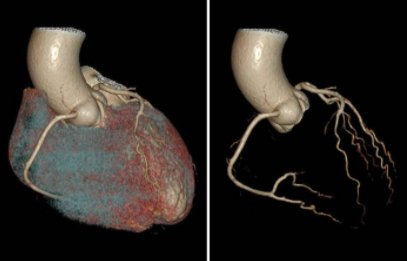

其中,冠状动脉CTA是一项无创性血管检查技术,该技术在冠心病的筛查、术前病情评估、冠脉变异和畸形的评价、心功能分析等方面发挥着重要作用,冠状动脉CTA检查已成为排除冠心病的重要手段,成功率在95%以上。冠状动脉CTA不但“无创”,而且其检查费用要比常规冠状动脉造影低得多,CT检查流程于门诊即可完成,无需住院。

冠状动脉CTA可以用于诊断冠心病、冠状动脉粥样硬化板块及管腔狭窄程度分析、血管走行分析(浅肌桥-壁冠状动脉分析);心脏肿瘤诊断、粘液瘤、室壁瘤、瓣膜疾病、房缺、室缺等室血管病变。